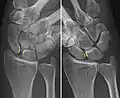

Dynamic instability: Increased scapholunate distance (between yellow lines) upon ulnar deviation of the wrist, but not otherwise. Dynamic instability: Increased scapholunate distance (between yellow lines) upon ulnar deviation of the wrist, but not otherwise.